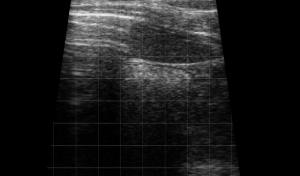

SIMON Ultrasound Database

This ultrasound database is a free resource for students and doctors!

Our collection includes videos of dogs, cats, horses, cows, humans, and many other species!